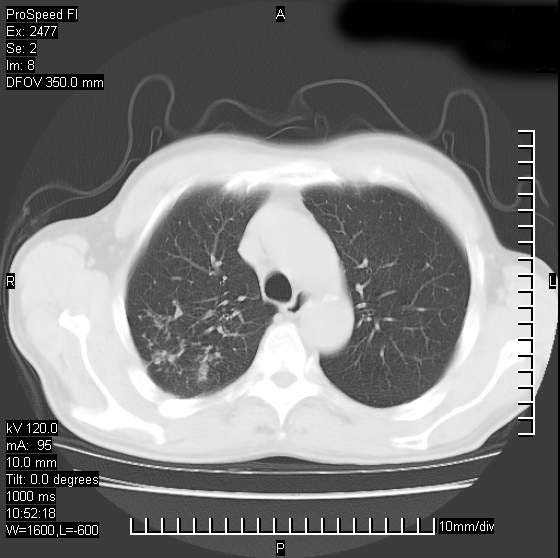

以下是引用天南地北在2007-10-9 14:29:00的发言:[br]1:右上肺结核[br]2:右肺下叶肿块:不支持肺癌,首先考虑炎性病变-肺脓疡可能性大[br]理由:1:临床病史支持,肺脓肿症状不明显应该是不规则服药造成。[br] 2:肿块边缘模糊,周围可见炎性渗出,长毛刺,内见支气管征,不过有点不规则。[br] 我感觉下肺癌这个诊断有点偏左,建议积极抗炎治疗后复查

以下是引用卜一在2007-10-9 15:55:00的发言:[br][br] [br] 1:右上肺结核[br]2:右肺下叶肿块:不支持肺癌,首先考虑炎性病变-肺脓疡可能性大[br]理由:1:临床病史支持,肺脓肿症状不明显应该是不规则服药造成。[br] 2:肿块边缘模糊,周围可见炎性渗出,长毛刺,内见空气支气管征,不过有点不规则。[br] 我感觉下肺癌这个诊断有点偏左,建议积极抗炎治疗后复查![br]支持! [br] [br] [br]

以下是引用wxy7406在2007-10-9 21:02:00的发言:[br]结合临床病史首先考虑感染性病变,但周围型肺癌不能除外,1.患者年龄偏大2.临床有咯血3.(也觉得是最重要的一点)病灶内有偏心性空洞。

以下是引用王仕学在2007-10-9 13:48:00的发言:[br]右下肺周围性肺癌可能性大,最好活检吧

以下是引用hhcckk在2007-10-9 15:18:00的发言:[br]右上肺病灶考虑结核,病灶多种形态并存(纤维化、增殖性病灶并存)[br]右下肺病灶比较难说,个人意见更趋向于“天南地北”的诊断----肺脓肿[br]1、病人有明显的寒战,高热,肿瘤病人很少出现[br]2、病灶周围的肺纹理走向柔和,没有肿瘤病灶常见的集束征[br]3、病灶边缘的毛刺较长,恶性肿瘤多为短毛刺[br]痰中血丝和病人的年龄是两个不利于良性肿块的因素,建议早点活检

以下是引用ydx_74在2007-10-9 15:53:00的发言:[br]右上肺结核,右下中心性肺癌可能大,肺门淋巴结肿大。